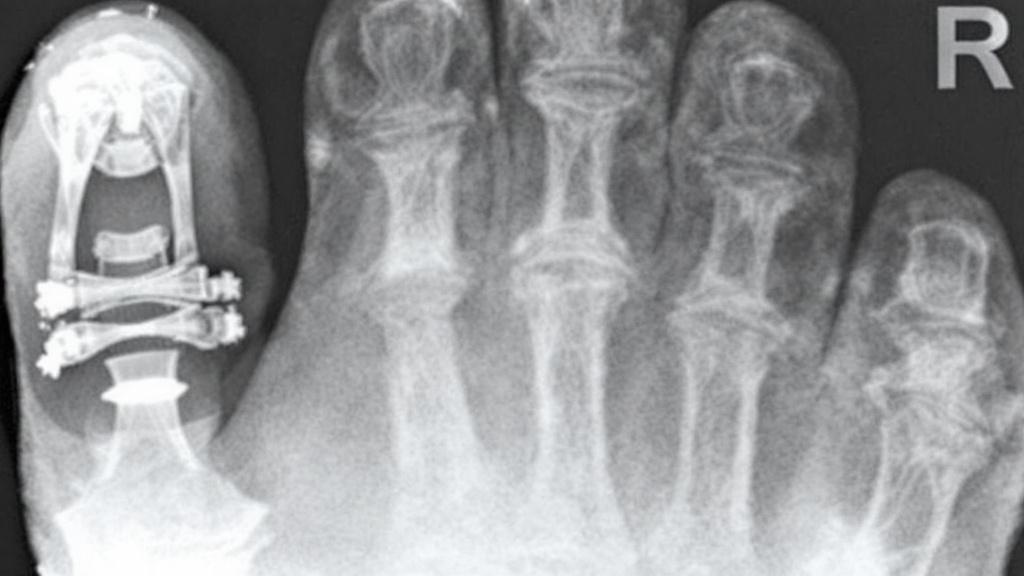

Название звучит сложно, но хирургическая суть довольно изящна. «Шеврон» — это V-образный вырез. Если вы помните нашивки на рукавах военной формы, то сразу поймете, о чем речь. Во время операции хирург делает именно такой, похожий на галочку, распил на первой плюсневой кости.

Многие думают, что врач просто «срезает шишку». На самом деле шишка — это лишь следствие того, что кость отклонилась в сторону. Хирург работает с причиной. С помощью V-образного распила он сдвигает головку кости обратно, в ее природное положение, и выравнивает большой палец. Благодаря такой форме распила костные фрагменты очень плотно прилегают друг к другу. Это дает высокую стабильность — кость надежно держится, пока срастается.

Хирург удаляет костный нарост, выполняет шевронный распил и смещает кость в правильную позицию. Чтобы результат закрепился надежно, кость фиксируют крошечным титановым винтом. Этот винт полностью прячется внутри костной ткани. Он не будет прощупываться под кожей, не зазвенит на рамках в аэропорту и, как правило, остается в ноге навсегда. Повторная операция по его извлечению обычно не требуется.